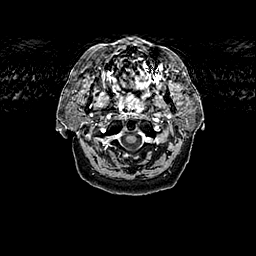

Glioma overlay -- Slice #1

[Home][Help][Clinical] Slice 1